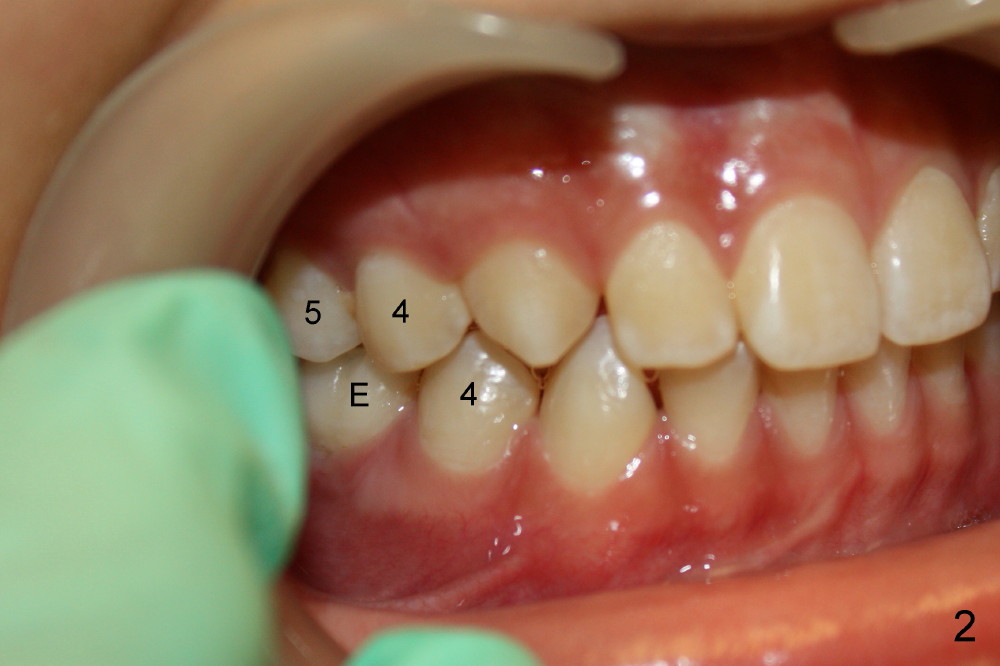

Two lower 2nd bicuspids are congenitally missing in a 11-year-old boy (Fig.1).  The lower left  (LL) E has been extracted due to caries.  There is severe periapical radiolucency associated with the LL6.  Root canal therapy (RCT) is being carried out for this molar with difficulty.  In addition, the boy is a dental phobic, refusing to have the lower right E extracted in spite of DO caries and pain.  In order to reduce the chance of future surgery, including extraction, there are two orthodontic plans to move the lower molars mesially.  Fig.2-4 show that the anterior occlusion and right posterior interdigitation is nearly within normal limit, whereas the left is not.

If RCT is successful for the lower left 1st molar, the lower right E is to be extracted.  All of the lower molars (including the third molars (Fig.5 *) will be moved mesially so that the final molar occlusion is Class III bilaterally.  This is Plan A.

Plan B is shown in Fig.6 when the LL 6 has to be removed due to RCT failure.  The orthodontic movement remains the same except LL6.  The edentulous space will be kept until the patient turns 18 years old.  An implant is placed (black box) and a crown is installed (red outline).